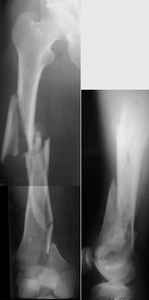

THX, initial images are

1,

2.

KEMMD> - Your last posted case: how is possible to have secure fixation with

KEMMD> applied construct without additional casting, bracing or Ilizarov?

At that moment we had in stock only the 10 mm solid nails so of course there was no idea about early weight bearing. But it was quite enough for early knee ROM excersises (see attached). Two locking screws through the distal block provided that.